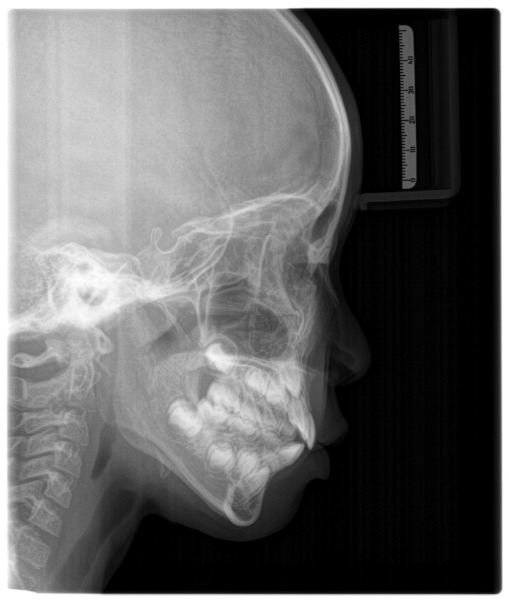

アクティビティー項目が終わった際にはレントゲンなども撮影し確認しています。

レントゲンの写真です。

気道の太さが大きくなったこと、顔の角度もまっすぐ前に出ています。